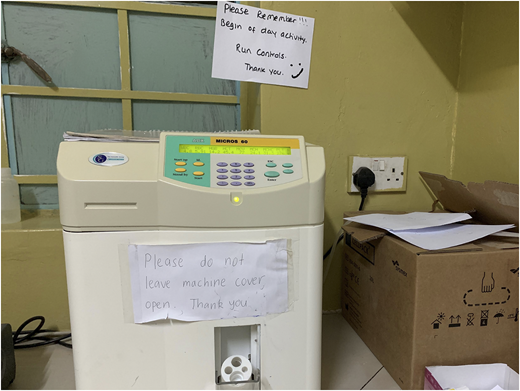

Performing QC for blood count analyzers

The rates of performing of quality control (QC) and preventive maintenance were low. So procedures were established that require daily QC; daily, weekly, and monthly preventive maintenance; and engineer servicing and documentation once every 6 months. A laboratory manual incorporating SOPs is also planned. A program for exchanging samples was arranged with the provincial Chipata Central Hospital Laboratory (Chipata, Zambia). Our laboratory staff were educated on the importance of performing QC. Data were collected retrospectively measuring documented QC completion in the hematology laboratory before the intervention (third quarter [Q3] and Q4 of 2018) and after the intervention (Q1 and Q2 until June 16, 2019) for blood count analyzers (Figure 7). Pearson’s χ2 test was applied to the data, and the result showed significant improvement in QC performance (P < .001) (Tables 5 and 6).

The importance of preventative maintenance and QC on the quality of laboratory results has been a point of focus at SFH. This photo shows our HORIBA ABX Micros 60 automated hematology analyzer used for in-vitro diagnostics testing of whole blood specimens.

The importance of preventative maintenance and QC on the quality of laboratory results has been a point of focus at SFH. This photo shows our HORIBA ABX Micros 60 automated hematology analyzer used for in-vitro diagnostics testing of whole blood specimens.